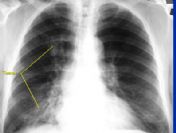

Komisyon Başkanı Aydın, "Çevresel faktörlerde farkındalık oluşturduğumuz zaman yüzde 95'in yüzde 50'lere ineceğini düşünüyoruz. Nüfusun yüzde 60'ının sağlıksız kiloda olduğunu görüyoruz. Akciğer kanserinin en önemli nedeni sigaradır" dedi.

Dünyada kansere birinci evrede tanı konulurken, Türkiye'de dördüncü evrede tanı konulduğunu ve yaşamın devam ettirilmesinin de yüzde 40 oranında gerçekleştiğini ifade eden Aydın, Kanser Erken Tarama ve Teşhis Merkezlerinde (KETEN) tüm işlemlerin ücretsiz olarak yapıldığını söyledi.